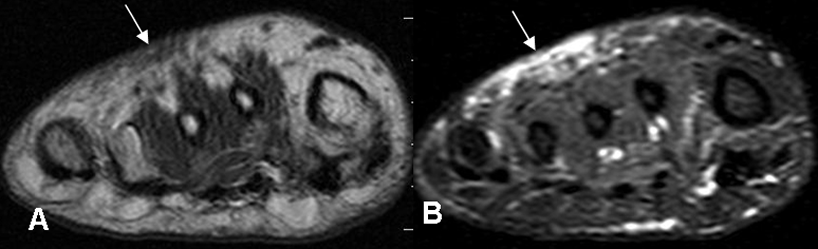

En la infección no complicada se encuentra engrosamiento de la piel, la fascia muscular, septación de la grasa subcutánea y captación variable del contraste, tanto en la TAC como la RM. (2, 12). (Fig 12 y 13).

Las lesiones son hipointensas en T1, hiperintensas en T2 y STIR. (12).

Fig 13. Celulitis.

A: RM coronal en T1 y B: RM coronal en STIR. Edema de tejidos blandos en el dorso del pie, por celulitis. No hay compromiso óseo.